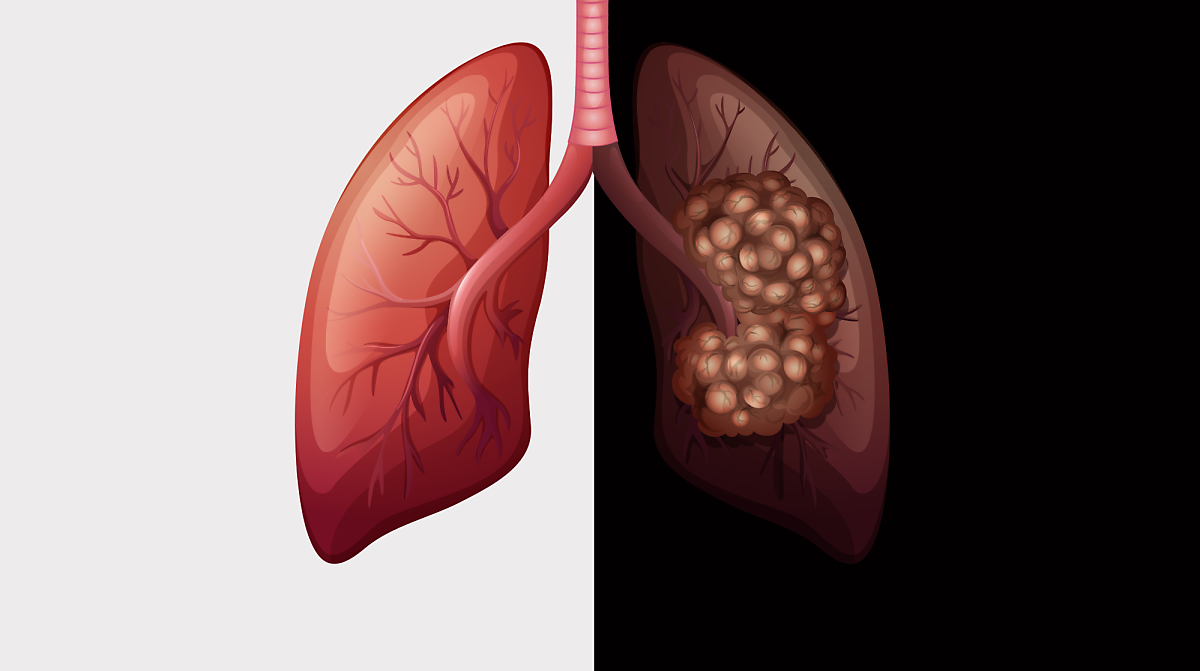

안녕하세요! 오늘은 ‘폐렴’의 증상에 대해 자세히 알려드릴게요

요즘처럼 일교차가 크고 면역력이 떨어지기 쉬운 계절에는

감기나 독감 뒤에 폐렴으로 악화되는 경우도 많습니다.

특히 노약자, 만성질환자, 어린아이에게는 치명적일 수 있죠.오늘은 초기에 알아두면 생명을 지킬 수도 있는

폐렴의 주요 증상 10가지를 아주 상세히 알려드릴게요.